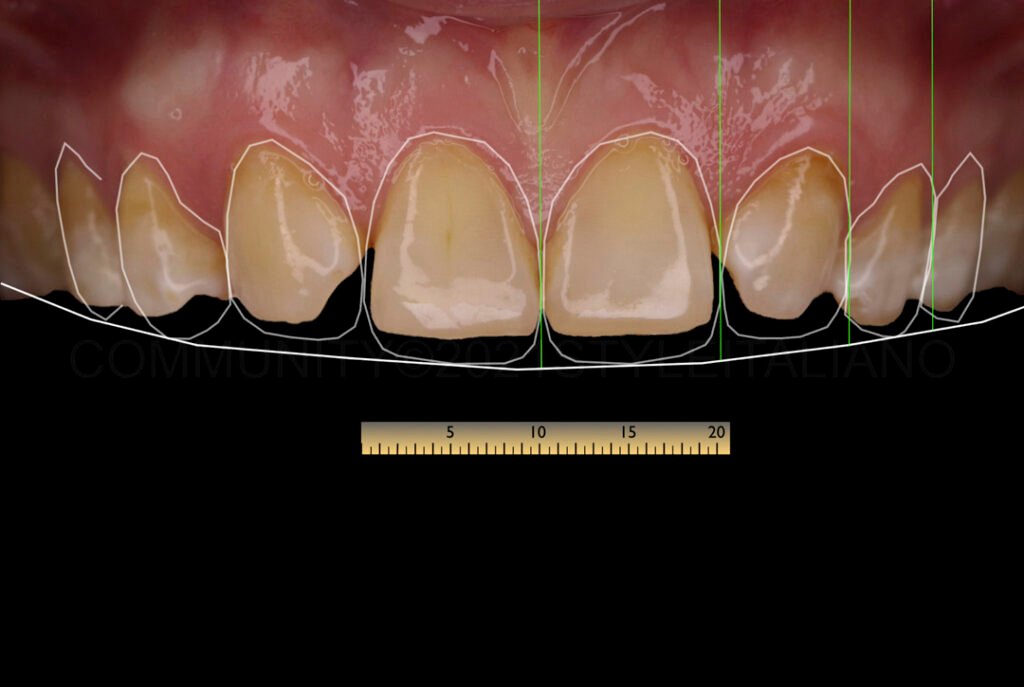

- Morphologie coronaire : La forme des canines (pointues ou arrondies) et des incisives supérieures (épaisses ou fines) influence l’esthétique finale. Des canines pointues peuvent rendre la solution 1 plus appropriée.

- Teinte des canines : Si les canines sont très jaunes, la conservation des espaces (solution 1) est souvent préférée pour éviter un contraste inesthétique.

- Coronoplastie : Réalisée avant le traitement orthodontique pour ajuster la forme des dents.

- Finition esthétique : Reconstitution des angles des dents à l’aide de composites chargés.

Intégration des Aspects Esthétiques et Fonctionnels

Le traitement des agénésies dentaires ne se limite pas à la correction orthodontique ou prothétique. L’esthétique faciale et dentaire joue un rôle crucial dans la satisfaction du patient. Par exemple, la teinte et la forme des dents doivent être harmonisées pour éviter des contrastes inesthétiques. De plus, la fonction occlusale, notamment la protection canine ou de groupe en latéralité, est essentielle pour prévenir les troubles de l’ATM.